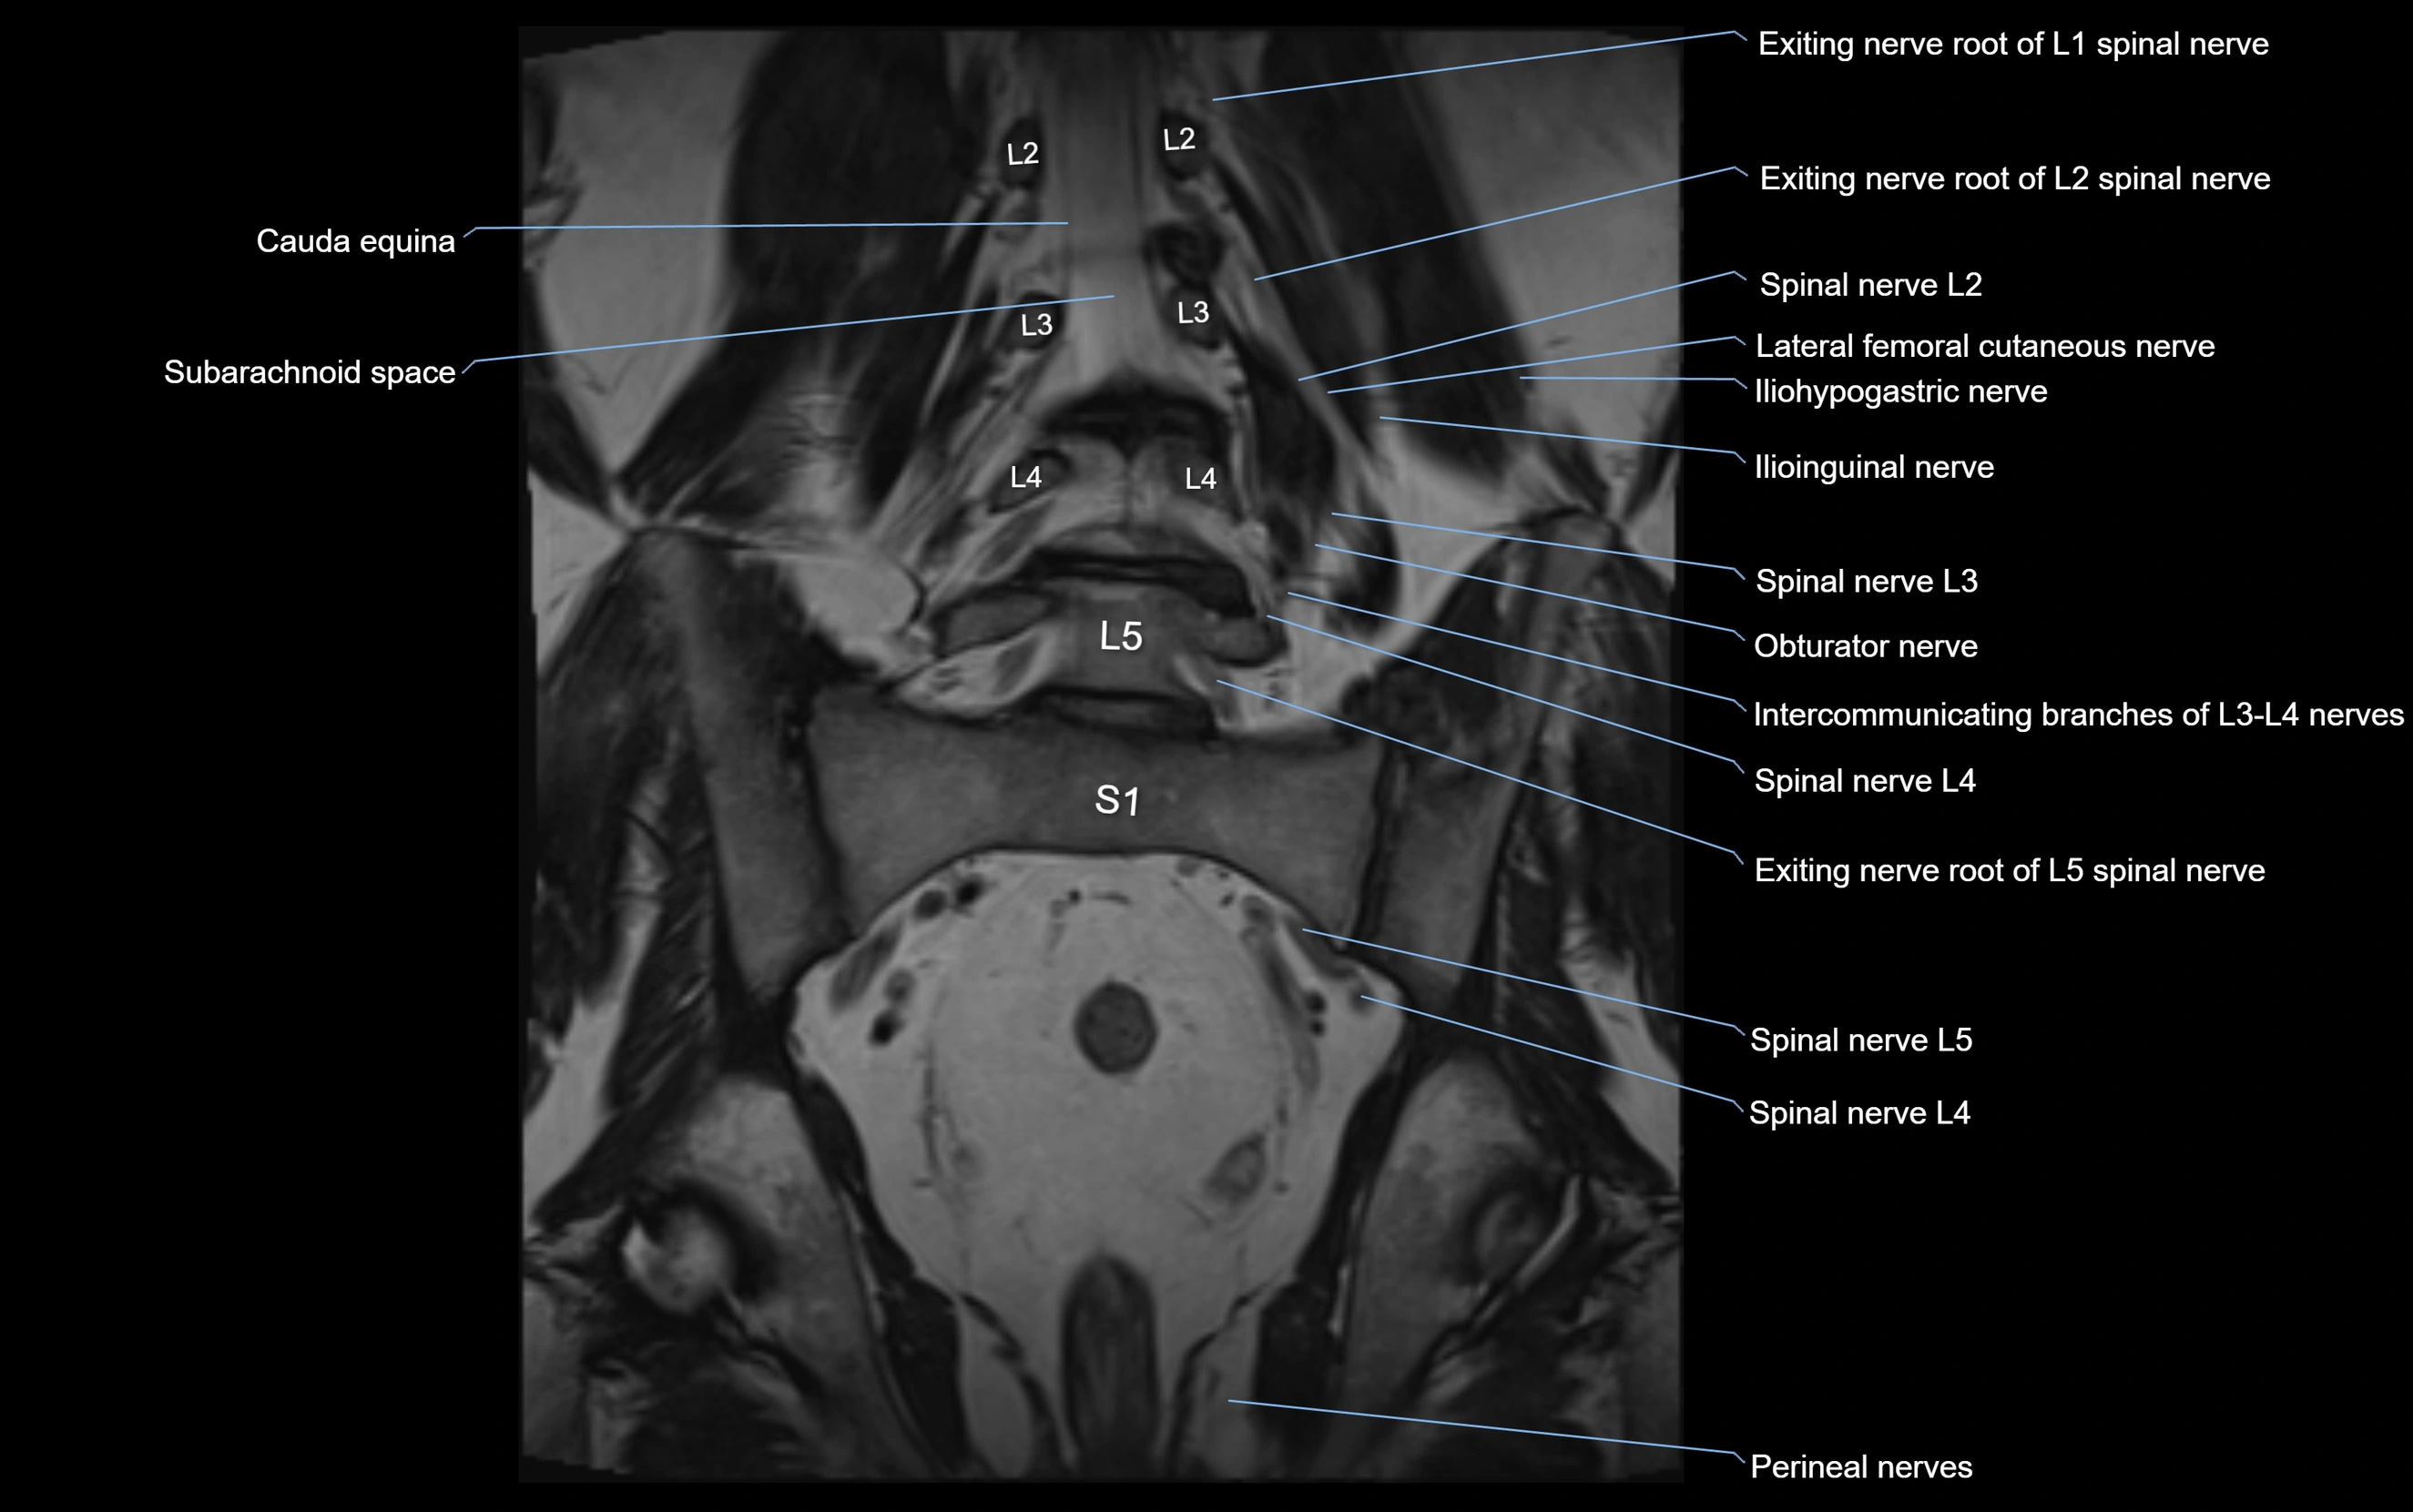

MRI image

image